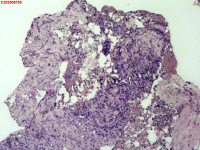

- 右侧胸壁穿刺组织活检

| 性别 | 女 | 年龄 | 81岁 | 临床诊断 | 胸锁关节结核? |

| 一般病史 | 胸部CT示:右肺下叶小结节,建议3-6个月复查,必要时胸外科会诊。左肺上叶多发小斑点、结节影,结核可能。右肺上叶多发点状影。双肺间质性改变。纵隔淋巴结肿大、钙化。右侧胸锁关节见骨质破坏,周围见软组织肿胀。 | ||||

| 标本名称 | 右侧胸壁穿刺组织活检 | ||||

| 大体所见 | B超:体表包块彩超示右侧胸壁混合回声包块,右侧胸壁低回声区,CDFI示:其内未见明显血流信号。 | ||||